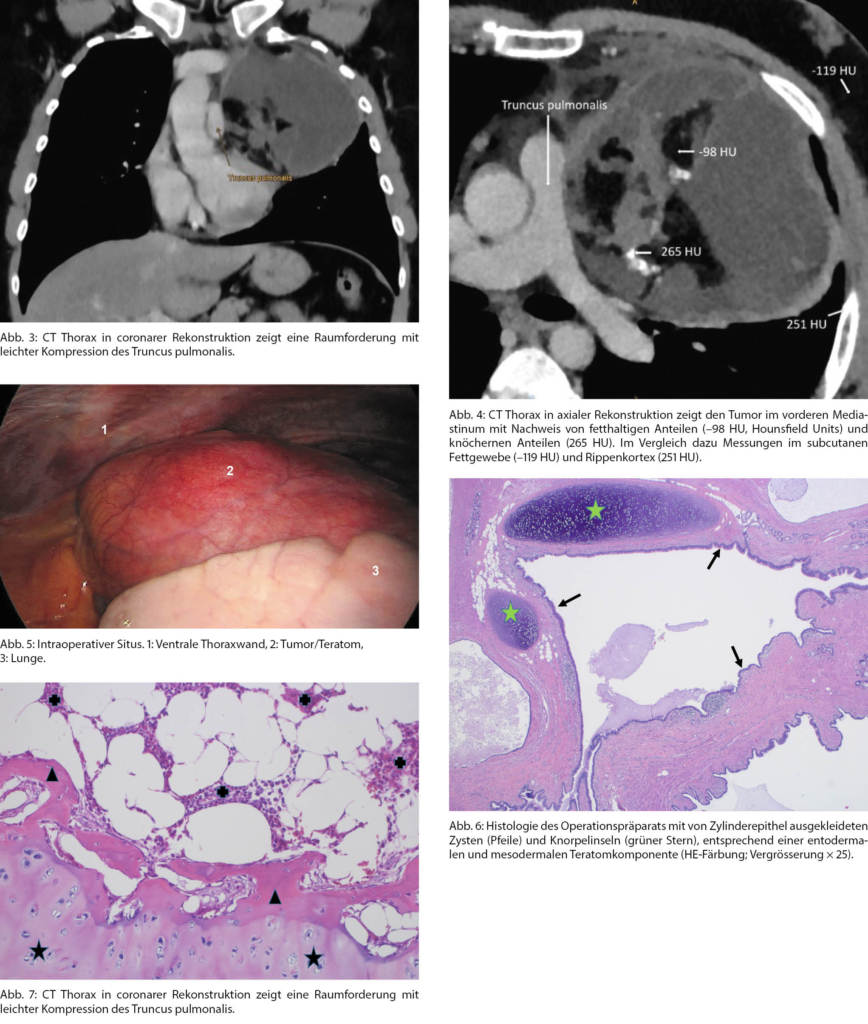

- Seltene Diagnose für einen Patienten mit Schulterschmerzen: reifes Teratom des Mediastinums